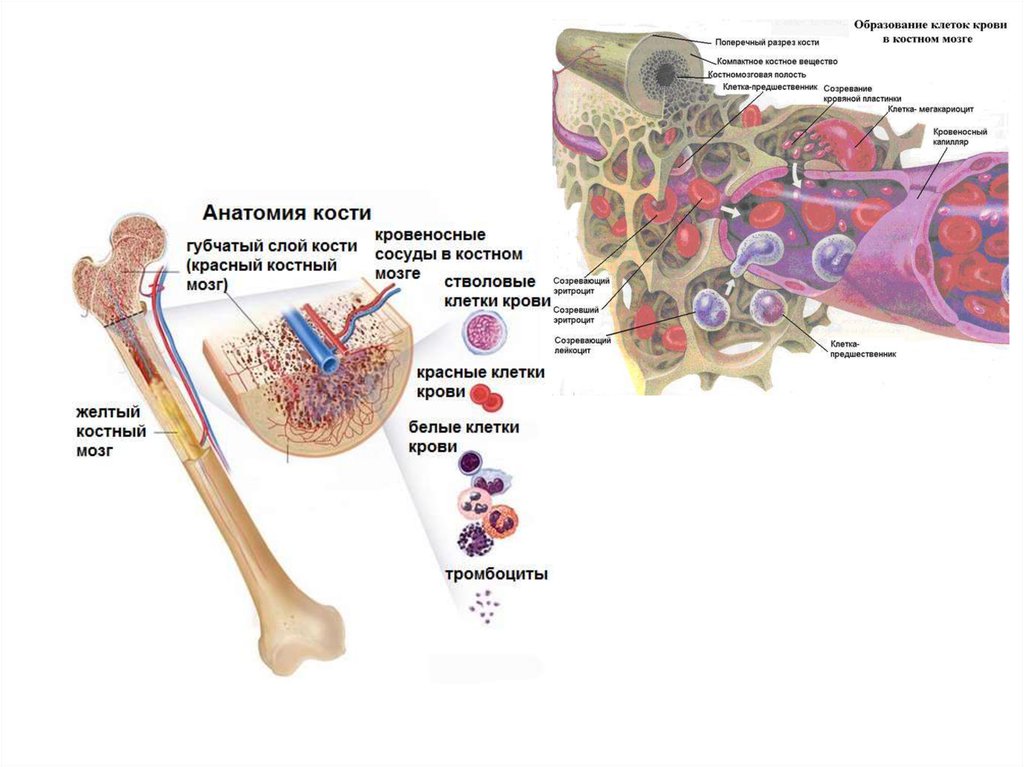

Изучение костного мозга: анатомия и функции

Раздел: Фотогалерея мыслей